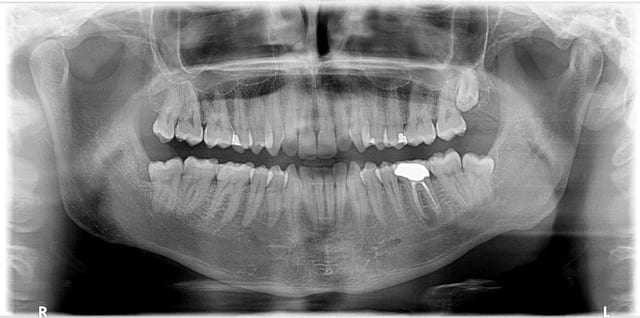

Je dis ca..... et on a du recul niveau quantité. Le dentiste conventionné francais est le moins conservateur au MONDE ! A tel point qu'il n'est nul besoin de passeport pour connaitre la nationalité de nos compatriotes, un simple pano suffit. Merci qui ?